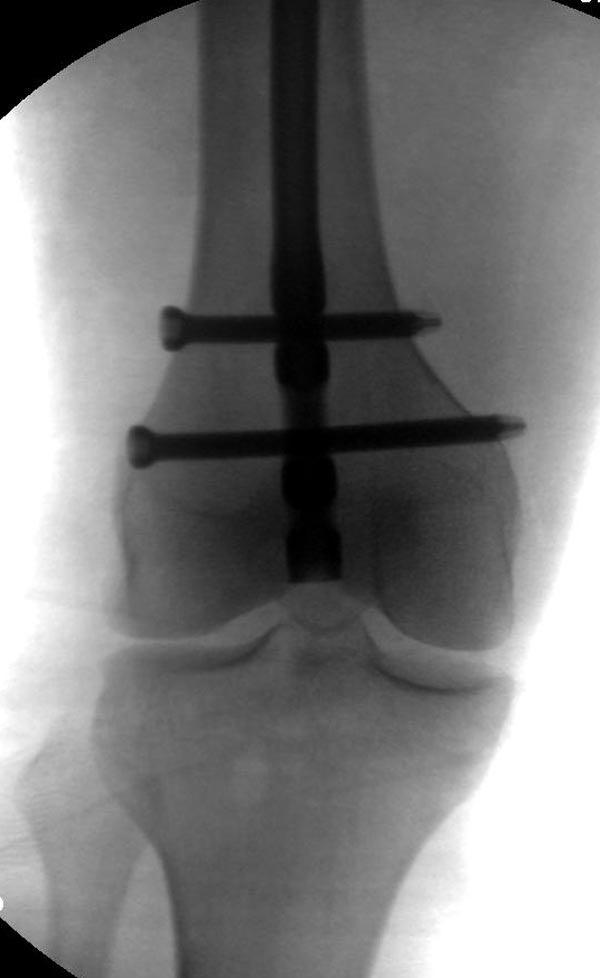

Пока надо делать снимки в классических укладках, т.е. хотя бы в двух проекциях. А по тактике из всех переломов: шейка является приоритетным и ургентным. Идеально фиксировать канюлированными винтами, но усложняется тем, что имеется перелом верхушки вертела. Навряд ли получится закрыто, надо открывать. Все зависит от возможностей на месте (писали насчет DHS), можно и интрамедуллярный гвоздь, но не надо укорачивать, только пустить overlapping, т.е. пластина от DHS покрывает часть гвоздя.

Здесь выставлен ренгенограммы больного, ему 21, травму получил в результате высокоскоростной погони на украденной машине, которая закончилась смертью трех остальных “боевых комрадов”. Начатую коллегой открытую операцию на шейке пришлось закончить мне, установкой винтов и ретроградной фиксацией бедра. Выписка в обычное сроки и наблюдался амбулаторно. Каждый раз напоминали о возможности осложнений ввиде несращения! По истечению 4 месяцев появились признаки варусной деформации. На СТ срезах несращение шейки и бедра. Риминг, замена на более толстый гвоздь и вальгусная остеотомия.